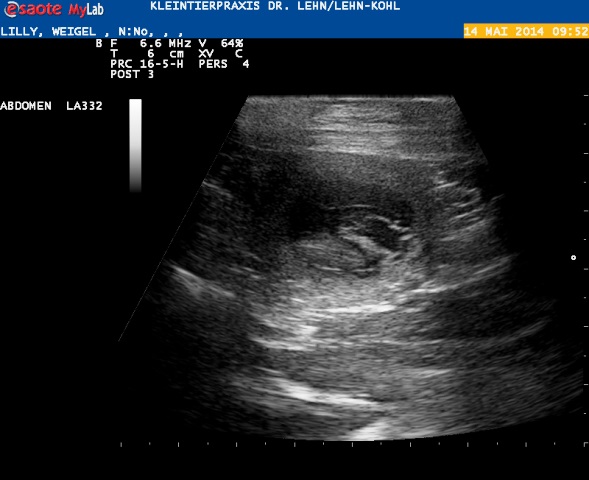

Wir mussten den Ultraschall auf heute verschieben :) hier kommen die ersten Fotos der H-ummelchen :)

Juhuu :) wir haben Herzchen schlagen sehen!

Hier sieht man schön die Fruchtblase und darin liegt unten der Welpe.

Oben kann man einen Teil der Nabelschnur erkennen :)